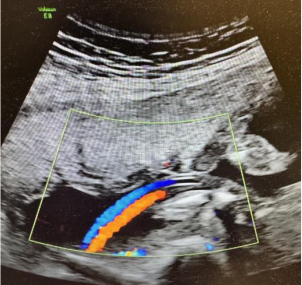

胎儿脐带内仅有1根脐动脉和1根脐静脉。孤立性单脐动脉与染色体异常无明显关系。约30%的单脐动脉合并其它结构畸形(心血管、泌尿生殖系统、骨骼系统、神经系统和消化系统等),发现时需排除其它结构畸形。目前,有一些研究显示孤立性单脐动脉与死胎及胎儿生长受限相关⑨,但是仍有另一些研究认为孤立性单脐动脉的胎儿生长受限的发生率并未增加⑩。尽管如此,一旦发现单脐动脉,应加强孕期监护及评估。